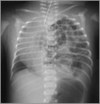

When are congenital diaphragmatic hernias usually detected? What would you see on CXR of baby with congenital diaphragmatic hernia?

* Diagnosed antenatally * See image for CXR